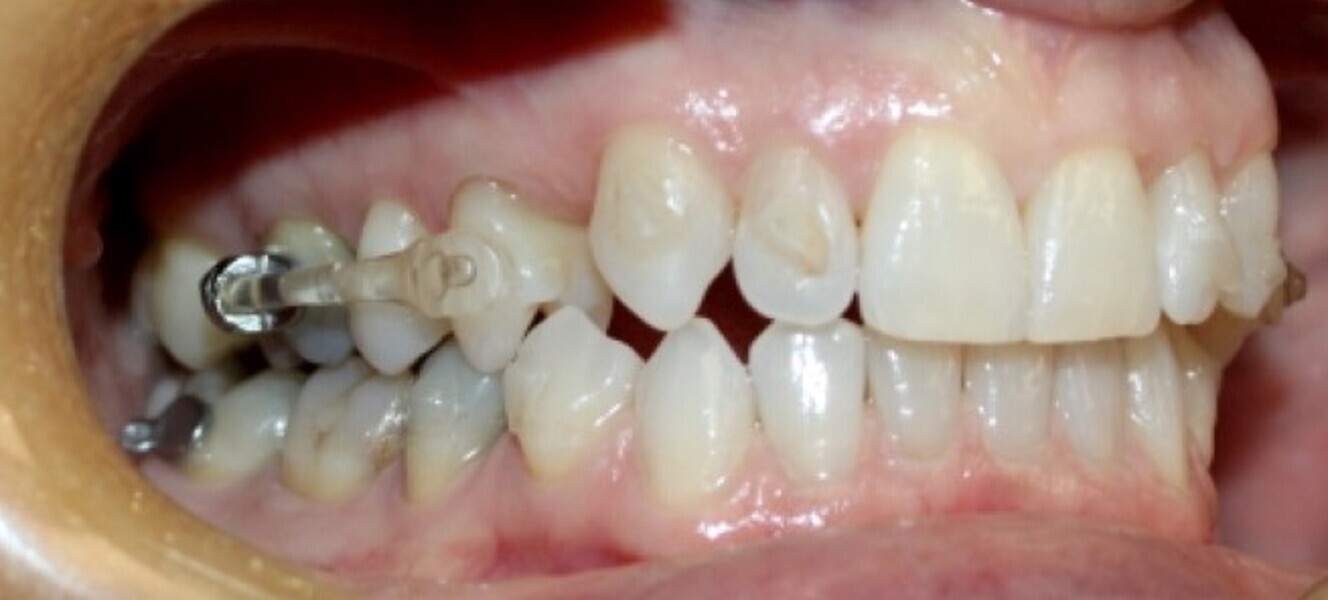

Fig. 19a: After six months of the Carriere Motion appliance and aligners. (a) Lateral view. (b) Occlusal view.

Fig. 19b: After six months of the Carriere Motion appliance and aligners. (a) Lateral view. (b) Occlusal view.

Aligners alone will fail because there are often significant skeletal components to Class III malocclusion, along with dental compensations, frequently making Class III a very difficult malocclusion to address with aligners alone. Instead use fixed Class III correctors off mandibular canines or first premolars, extending back to mandibular first molars or second molars, for a more assured, fast and profound Class III correction as the maxillary arch is aligning with clear aligners. An example of such a device is the Carriere Motion 3D Class III appliance (Figs. 20–22). The outcome is Class III correction that is much more predictable than with clear aligners alone.

Fig. 21: Carriere Motion Class III appliance in place.